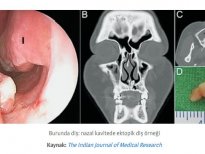

Diş yapısı en dıştan içe doğru mine (kök kısmında sement), dentin, pulpa olarak sıralayabiliriz. Mine, sement ve dentin hidroksiapatit kristalleri dediğimiz kalsifiye yapıdan oluşur ve büyük ölçüde kemiğe benzer. Hidroksiapatit kristalleri dişlere sertliğini verir ve dişlerin molekül yapısında eser miktarda su bulunduğundan dolayı oldukça serttir ve böylece çok büyük çiğneme kuvvetlerine dayanabilirler. Mine, vücuttaki en sert maddedir; öyle ki kemikten bile daha serttir. Bu kadar yoğun kalsifiye yapıların yumuşak dokuda gelişmeleri oldukça zor ve nadir olmasına rağmen çarpıcı örnekleri vardır.